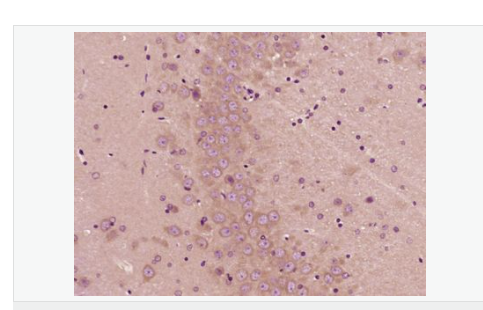

Rabbit anti-TSPO/PBR Polyclonal antibody

英文名稱TSPO/PBR

中文名稱外周苯二氮受體抗體

別    名BPBS; BZRP; DBI; IBP; Isoquinoline carboxamide-binding protein; MBR; mDRC; Mitochondrial benzodiazepine receptor; PBR; PBS; Peripheral benzodiazepine receptor; Peripheral benzodiazepine receptor-related protein; Peripheral type benzodiazepine receptor; pk18; PKBS; PTBR; Ptbzr; PTBZR02; RATPTBZR02; translocator protein (18kDa); Translocator protein; TSPO; Tspo1; Benzodiazapine receptor (peripheral); Benzodiazepine peripheral binding site.

研究領域細胞生物  免疫學  神經(jīng)生物學  轉錄調節(jié)因子  糖尿病  線粒體

產(chǎn)品應用ELISA=1:5000-10000 IHC-P=1:100-500 IHC-F=1:100-500 IF=1:100-500 (石蠟切片需做抗原修復)

分 子 量18kDa

細胞定位細胞漿 線粒體

免 疫 原KLH conjugated synthetic peptide derived from human PBR:31-130/169

產(chǎn)品介紹PBR (Peripheral type Benzodiazepine Receptor) is a ubiquitous protein (18 kDa) found in most steroidogenic tissues. It is located primarily in the outer mitochondrial membrane of steroid producing tissues and is found in association with a 34 kDa voltage dependent anion channel protein (VDAC). PBR interacts with some benzodiazepines and has different affinities than its endogenous counterpart. PBR appears to be a key factor in the transport of cholesterol from the outer to the inner mitochondrial membrane to permit the initiation of steroid hormone synthesis. It is thought to be part of the mitochondrial permeability transition pore (PT) and to be involved in apoptosis. It is speculated that patients with congenital lipoid adrenal hyperplasia, who cannot make any steroids, might have a genetic lesion in BZRP. A short form, PBRS is also expressed in the same tissues, but at a level about ten times that of PBR.

Responsible for the manifestation of peripheral-type benzodiazepine recognition sites and is most likely to comprise binding domains for benzodiazepines and isoquinoline carboxamides. May play a role in the transport of porphyrins and heme. Plays a role in the transport of cholesterol across mitochondrial membranes in steroidogenic cells.

Mitochondrion membrane.

Found in many tissue types. Expressed at the highest levels under normal conditions in tissues that synthesize steroids.